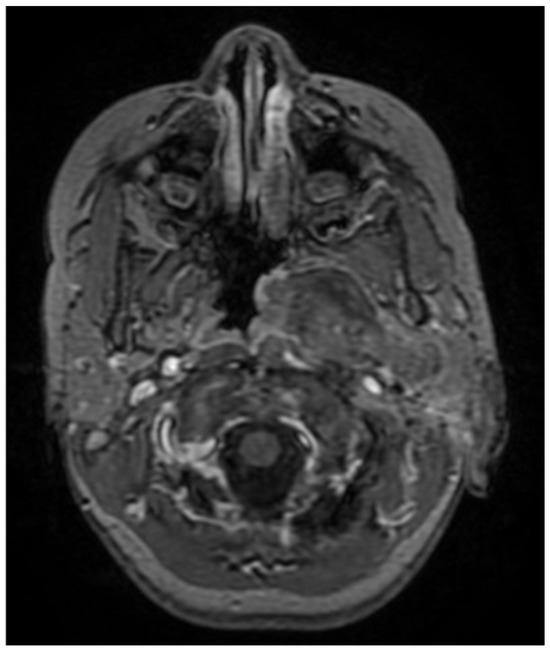

A CNS MRI was performed, which reveal a large lobulated formation in the oropharynx and nasopharynx with left tonsil involvement, spreading to the retropharyngeal space and propagating through the left Eustachian tube into the middle ear. The previously formed surgical cavity was completely infiltrated from the soft tissue tumour mass. Approximate dimensions of the lesion in the mastoid—25/45 mm. axial, 38/39 mm. coronal (Figure 6, Figure 7 and Figure 8).

Figure 6. MRI of the patient on postoperative day 17.

Figure 7. MRI of the patient on postoperative day 17.

Figure 8. MRI of the patient on postoperative day 17.